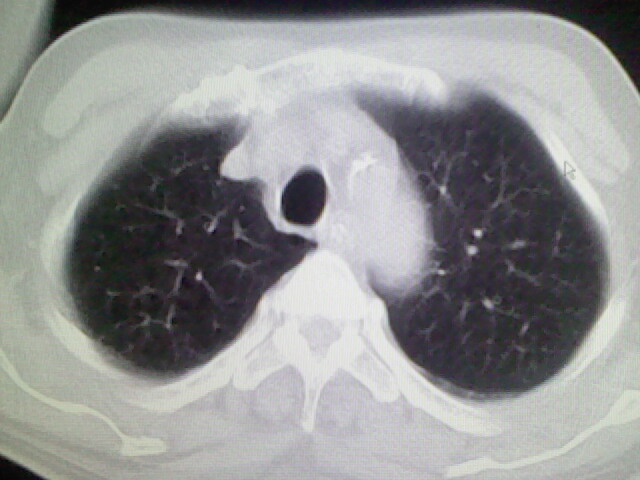

男,70岁,脑出血,长期卧床,左侧背部可触及肿块

慢性间质性炎症,与老年患者长期卧床相关,胸壁软组织及肋骨未见异常。

考虑右肺及左肺下叶炎症。

右肺肺气肿并炎症。

肺气肿并炎症。